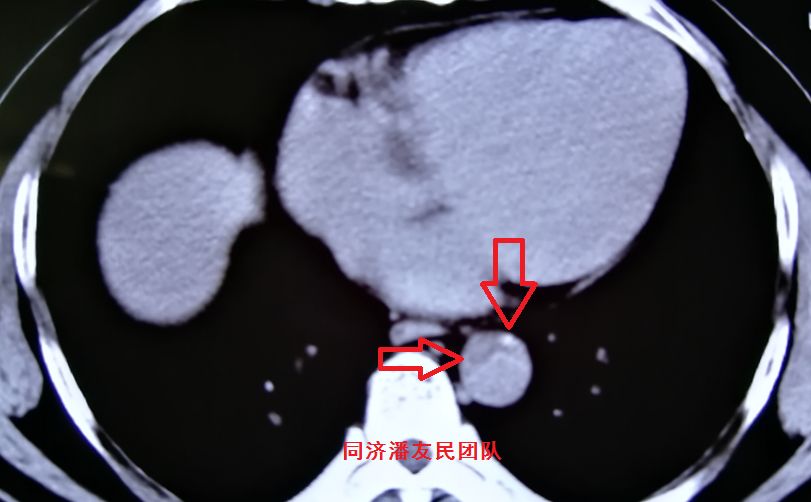

结果在上级医院复查胸腹主动脉CTA,在平扫CT提示主动脉夹层的对应层面,证实了主动脉夹层(图3~6)。同时发现升主动脉及主动脉弓均有夹层撕裂 (图7~8) 。 因此,正确诊断应该是 A型 (1型) 主动脉夹层。

图4:CTA显示图3相应层面,与平扫CT对应的血管内膜征及血管周围钙化点(红箭头所示)